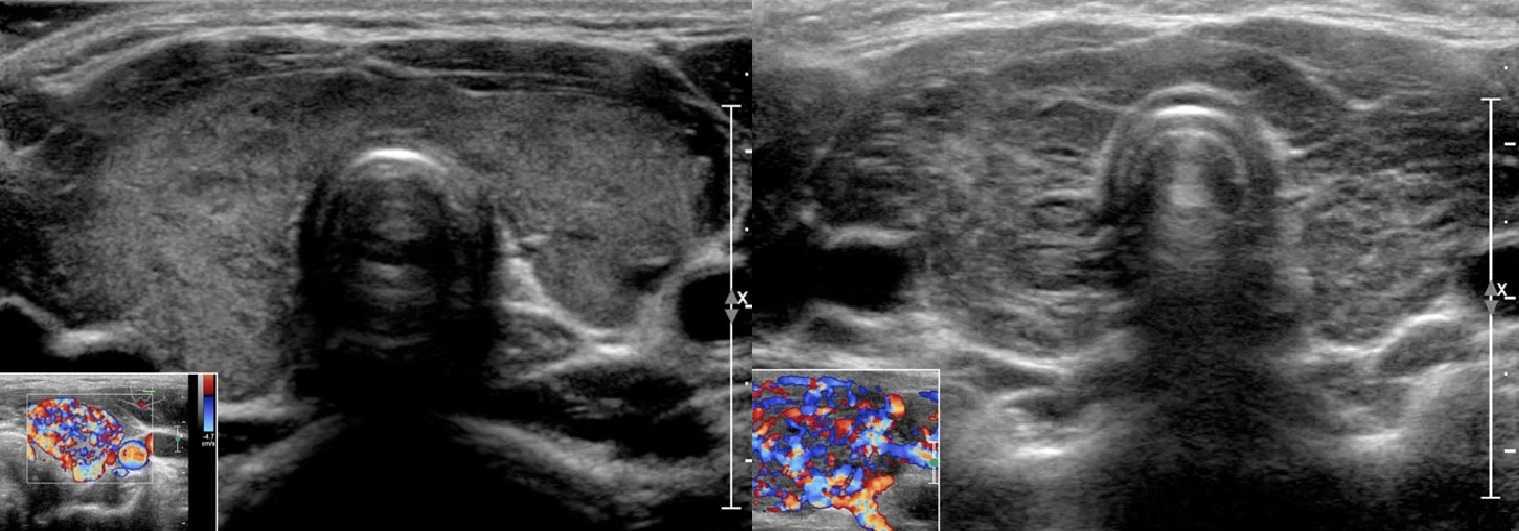

Диффузный токсический зоб (ДТЗ) на УЗИ

Ультразвуковые признаки ДТЗ близки гипертрофической форме АИТ. Нормальный размер железы может быть только в начале заболевания, затем она резко увеличивается и появляются признаки тиреотоксикоза. Возможны два варианта: в неизмененной паренхиме зияют гипоэхогенные «дыры» или эхогенность диффузно понижена. На фоне гипоэхогенных участков заметны тонкие гиперэхогенные структуры — междольковые перегородки. Они четко проступают из-за значительной разницы в акустических свойствах, а истинная фибротизация встречается редко. При ДТЗ кровоток усилен чрезвычайно — «пылающая» железа. PSV на верхней и нижней щитовидных артериях всегда выше 40 см/сек.

С началом лечения ДТЗ претерпевает обратное развитие – объем железы постепенно уменьшается, эхогенность повышается, а степень неоднородности снижается. При АИТ аномальная УЗИ-картина сохраняется на протяжении всей жизни пациента.

Рисунок. Выраженный кровоток при ДТЗ (1) и гипертрофической форме АИТ (2)

Обратите внимание, при ДТЗ гиперэхогенные структуры – очаги фиброза, не выражены, в отличие от АИТ

Рисунок. У пациента с тиреотоксикозом на УЗИ щитовидная железа увеличена, контур волнистый, паренхима умеренно гипоэхогенная, эхоструктура неоднородная, кровоток заметно усилен – «пылающая железа». Заключение: ДТЗ.